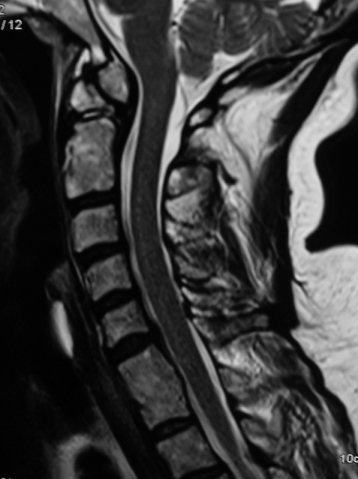

1999 Tarihli Servikal MRG - Os Odontoideum

Resim 1: 1999 tarihli (12 yıl önce çekilmiş) servikal MRG'de C6-C7 mesafesinde disk hernisi olduğu, aynı zamanda densin C2 gövdesinden koparak ayrı bir kemik haline geldiği (= os odontoideum) görülmektedir.